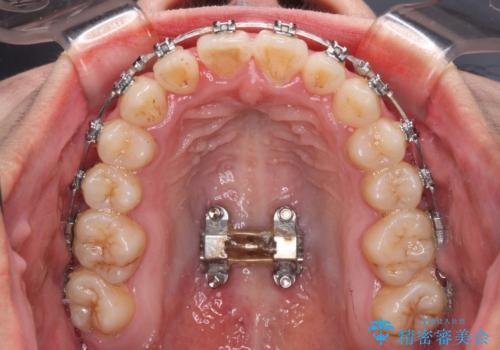

急速拡大装置 狭い上顎骨を拡大してワイヤー装置で短期間治療

上顎歯列が狭窄していたため、急速拡大装置により上顎骨を側方に拡大し、その後ワイヤー装置にて矯正治療を行うこととしました。

上顎骨を拡大することで、八重歯やデコボコを歯列に収めることができ、下顎の歯が外に位置していた奥歯の咬み合わせも改善することができました。